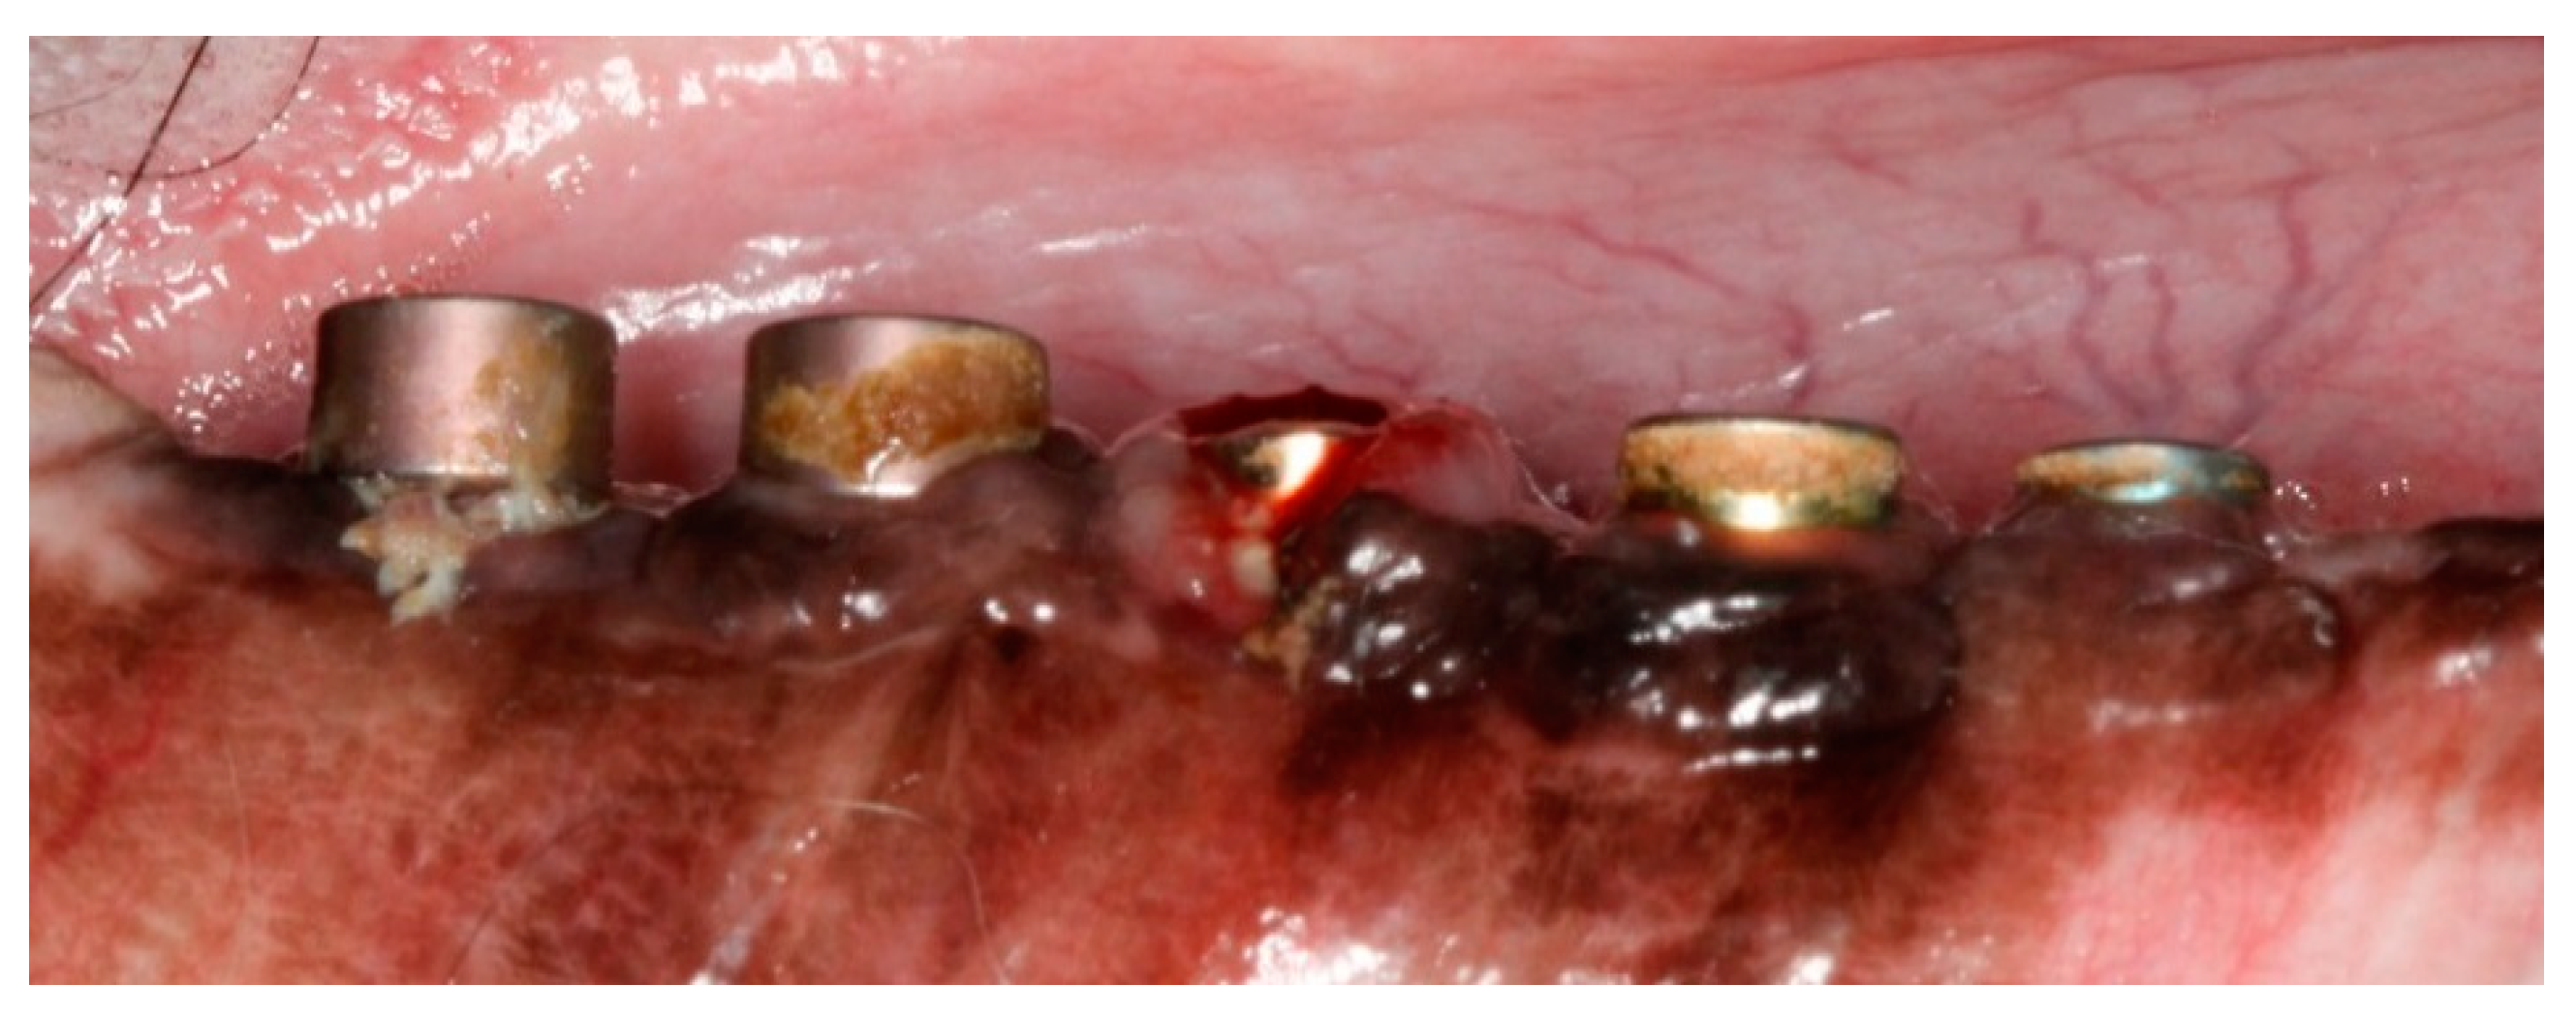

The premolars and the first molar were extracted after reflection of full thickness mucoperiosteal flaps from the posterior mandibular region on the right side. Three months later, five 8-mm screw-shape endosseous titanium implants were inserted in the edentulous regions using standard instruments and surgical techniques. Implants were exposed 3 months post-implantation and their healing abutments were connected. No oral hygiene regimen was administrated during this period, so that the peri-implant inflammation could initiate spontaneously. Five months post-implantation (two months post implant exposure), to accelerate the progression of the initial lesions, alternative cotton ligatures were placed according to the method described by Lindhe et al. [44] in a submarginal position around the neck of implant (Figure 1). The animal was then fed a soft diet to induce plaque accumulation and to provoke peri-implant inflammation and loss of bone.

Figure 1.

Post-operative image at 9-month post-implantation. Note the ligatures placed in implants 1, 3 and 5, and the subsequent local inflammation.